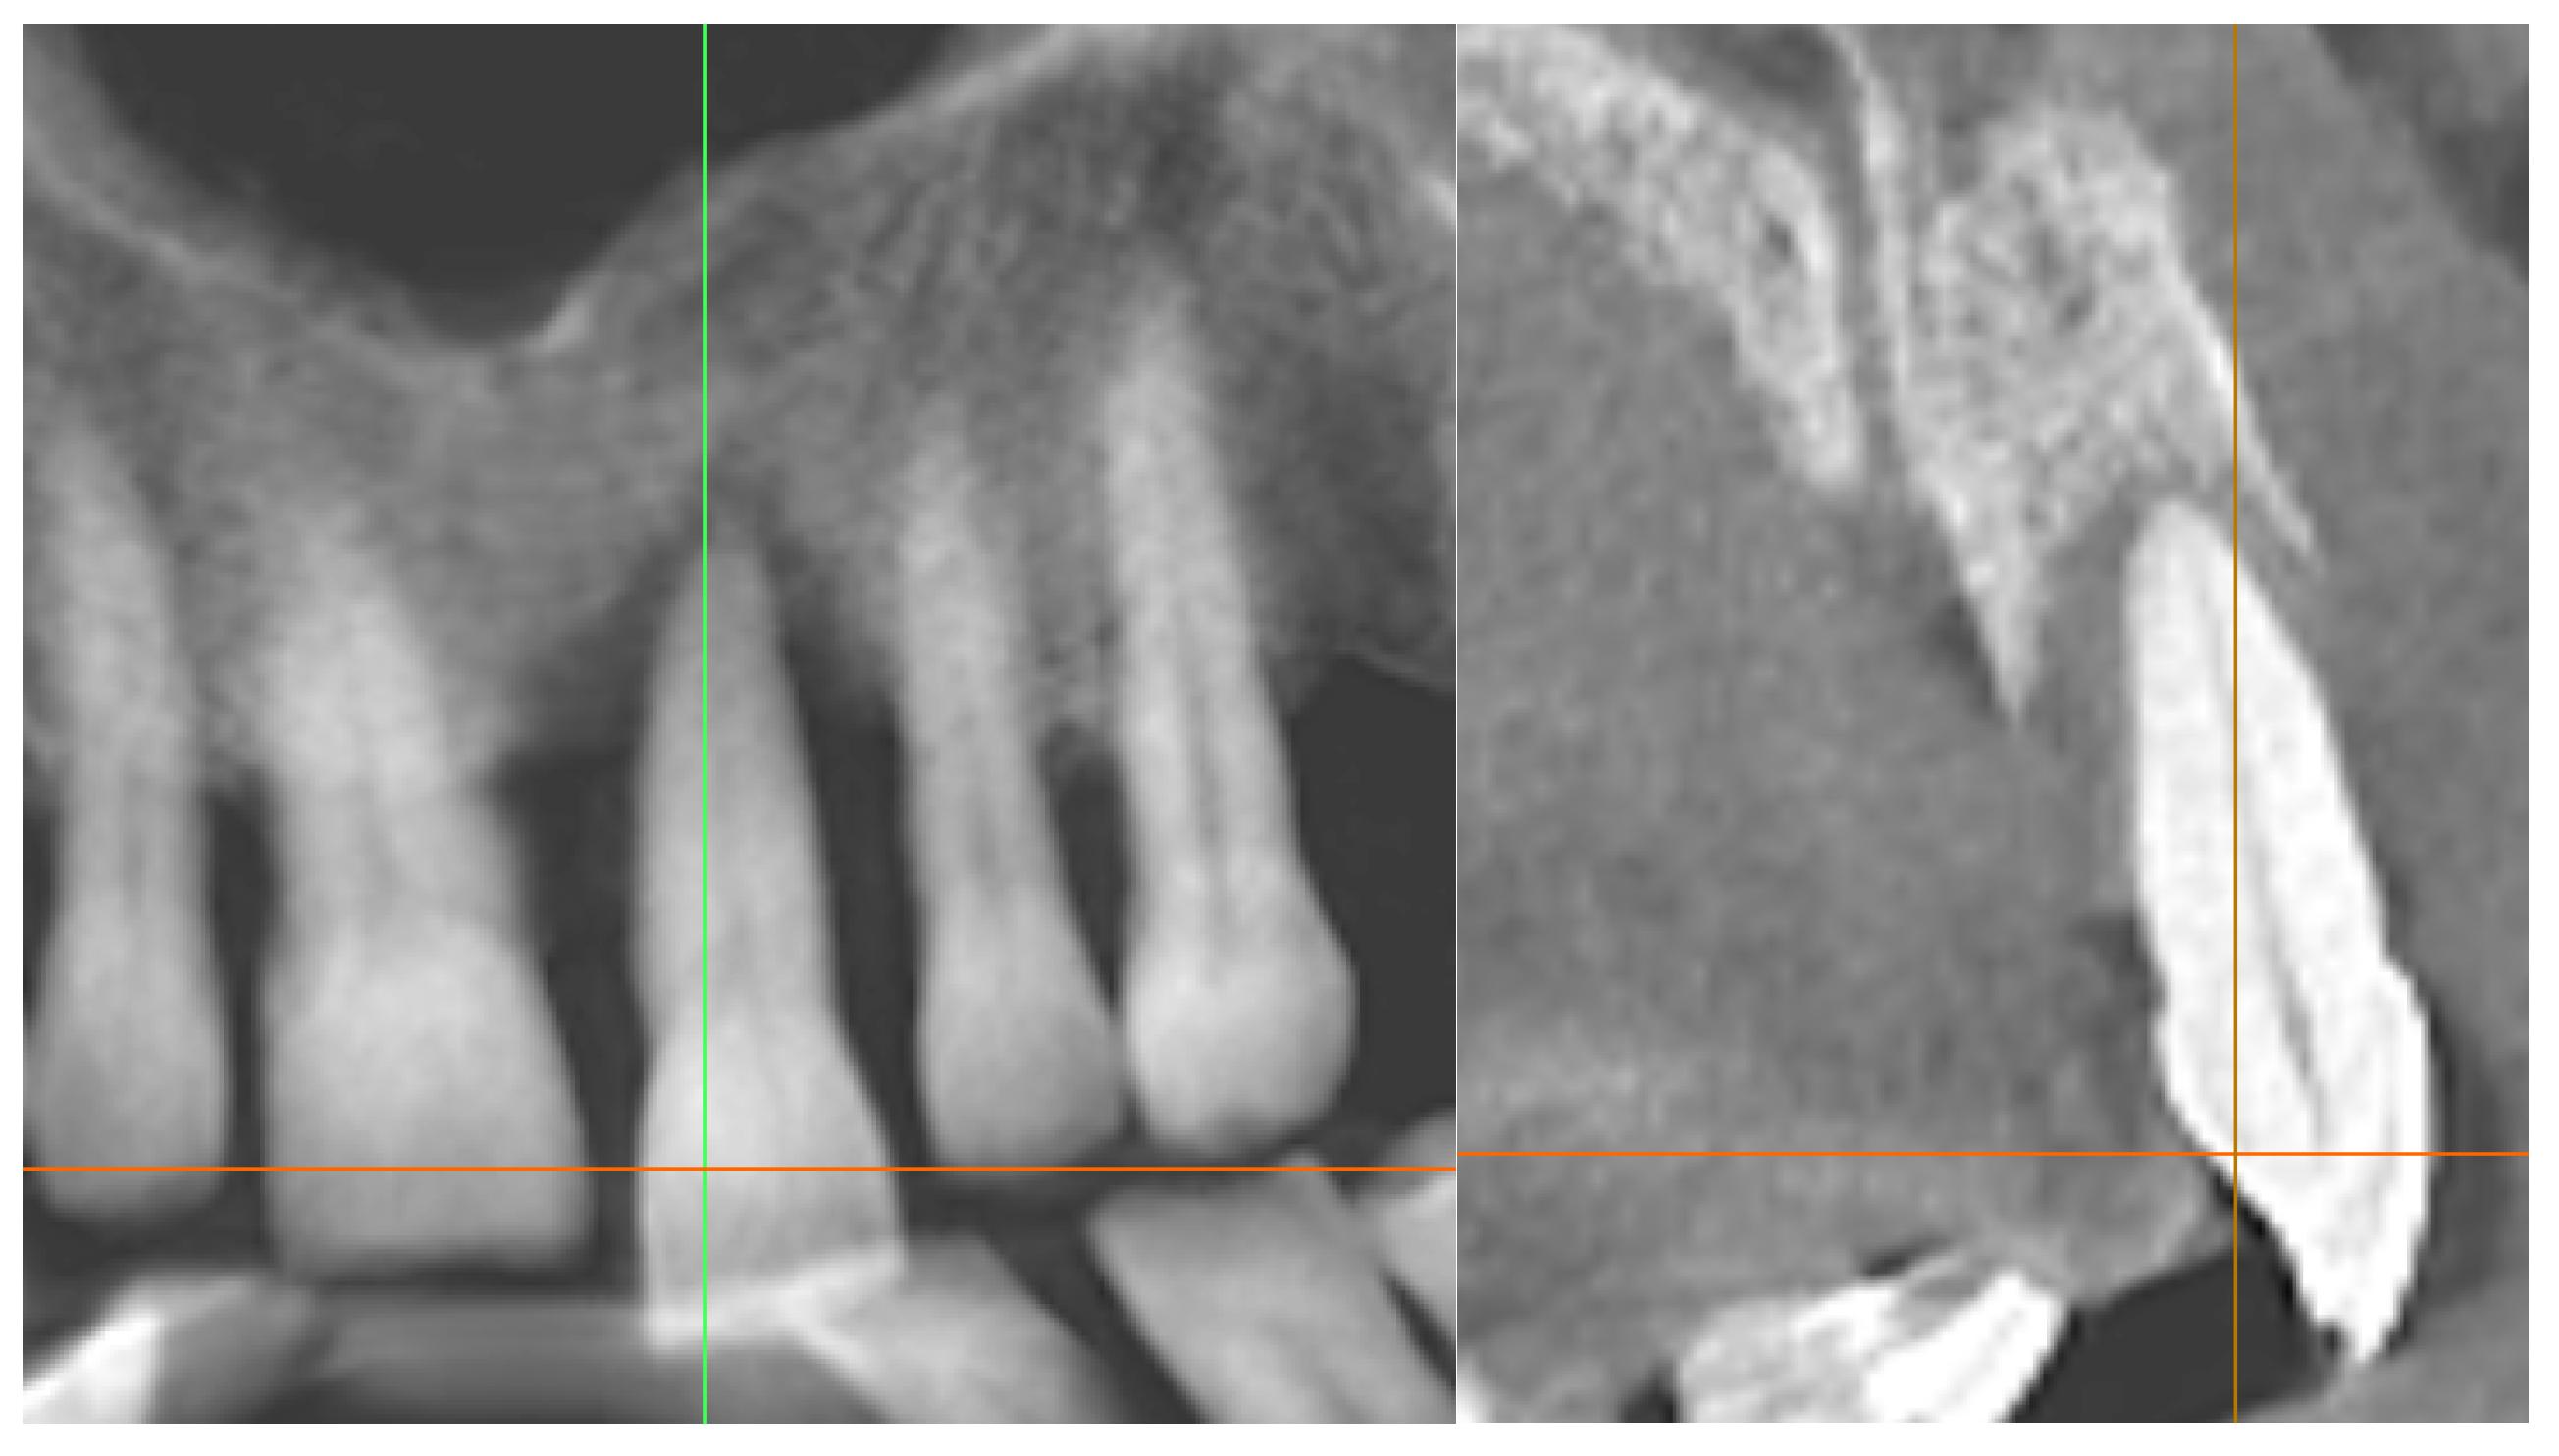

3.2. Radiographic Findings

4.3. Regenerative Approach and Endodontic Protocol